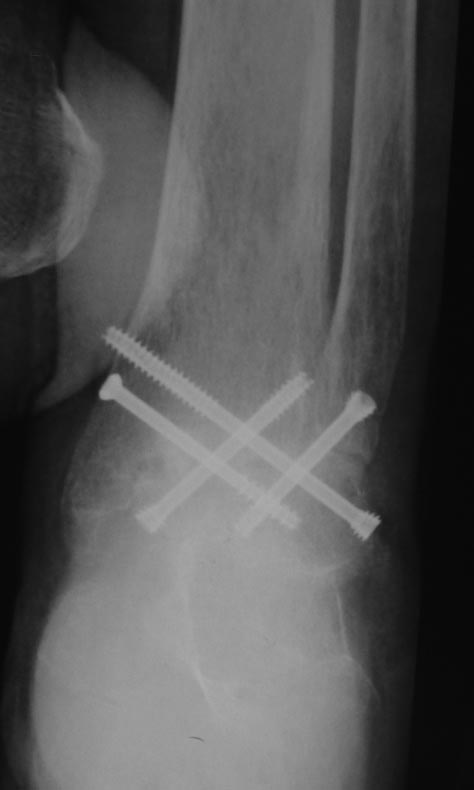

Вот обещанный в чем-то похожий случай. Пациентка 58 лет с тяжелым ревматоидным артритом. Оперировал в 2013 г. В одну сессию сделал чрескожно повторную операцию на стопе (раньше где-то оперировали, пациентка приехала издалека) и малоинвазивный артродез голеностопного сустава (имелась варусная деформация, как компенсация вальгуса колена, на фоне выраженной ревматоидной артропатии). А через неделю – протезирование коленного сустава (фиброзный анкилоз после когда-то выполненной синовэктомии, грубая вальгусная деформация). Понятно, что неделю между операциями стопа торчала в сторону и не была опороспособной. Основное пожелание по коленке было, чтобы сгибалась хоть немного для походов в театр. В конечном счете, сустав сгибался до 90 гр. Фотография стоя была прислана через 2 года после операций. А через 3 года, прошедшим летом, пациентка упала с лестницы: перипротезный перелом бедра. Через 5 дней приехала оперироваться. Отсюда отек на фото стопы. Что интересно, через 2 мес. после остеосинтеза пациентка написала, что только теперь, после перелома, смогла ощутить опору всей поверхностью стопы. До этого пользовалась индивидуальными стельками.